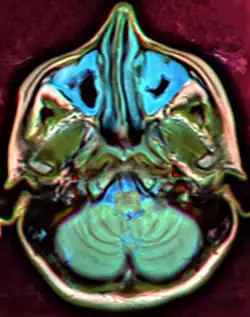

Ilustracja

Zapalenie zatok szczękowych w obrazie MRI